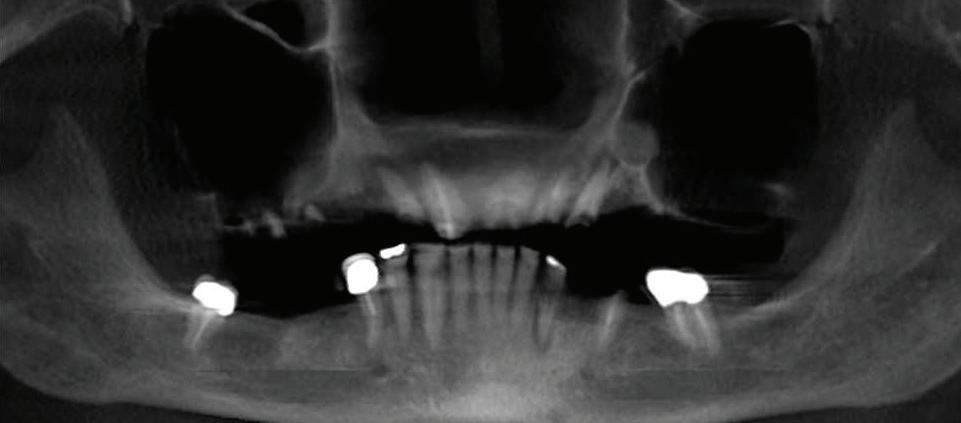

All-On-4 Dental Implants: A Reason To Smile Again

All-on-Four: One Full Arch Of Teeth, Four Dental Implants

To fully understand this remarkable technique for replacing teeth, you should first understand what a dental implant is. An implant is a small titanium screw that fits inside your jawbone and replaces the root-part of a missing tooth. Minor surgery is required to insert the implants. Once the implant is in place, a crown is attached to give you a highly realistic-looking and functional prosthetic tooth.

Here’s where it gets really interesting: You do not need a dental implant for each and every one of your missing teeth. All you need is four precisely placed implants on the top of your mouth, and four on the bottom, to restore your full smile. That’s the beauty of the all-on-four. And because the implant is made of titanium, it has the unique ability to fuse to living bone and function as part of it. So eventually, the dental implant becomes part of the jawbone and serves as a strong, long-lasting foundation for your new teeth.

Besides ensuring that your implants are permanently fixed in place, this bone fusion has another important benefit: it prevents future bone loss in the jaw. This helps to maintain a more youthful facial structure – and better oral health. But perhaps the biggest surprise about the all-on-four is how quickly it can transform your life.

What’s The All-on-Four Dental Implant Procedure Like?

It can be scary to get implants for the first time. Most of that fear is probably due to the uncertainty, so here is the step-by-step process for getting an All-on-Four dental implant.

First, your dentist will want to make sure your comfortable, so either local or general anesthesia will be administered.

Second, the dentist or surgeon will prepare your mouth for the implants, which involves removing your remaining teeth that are failing. They will then remove any diseased or infected tissue from your jaw and gums.

Next, they will begin the implantation process. This means they will insert the titanium screws into your jawbone. Most likely, they will place two implants toward the front of your mouth and two towards the back of your mouth so the “anchors” can evenly bare the force of the denture. After the implants have been placed, they will thoroughly clean the surgical sites and suturing all the